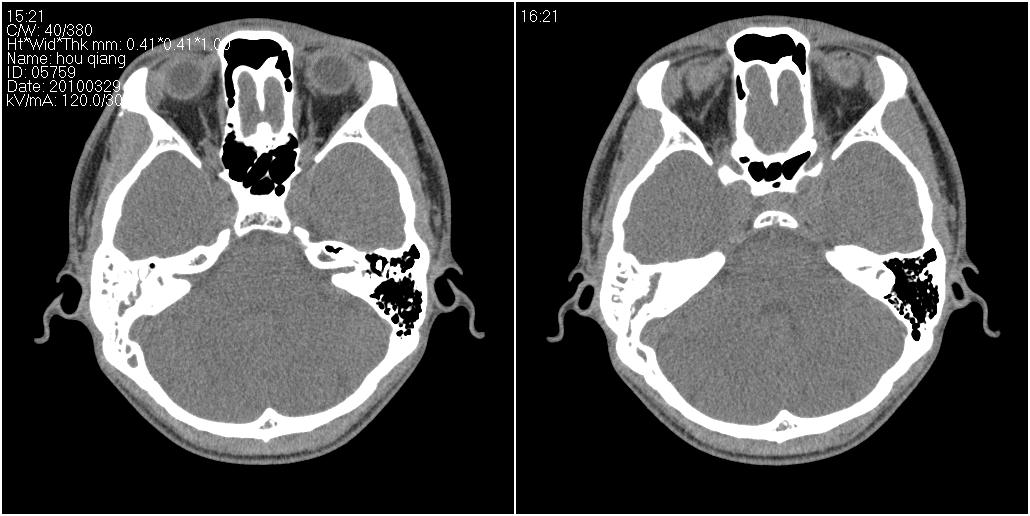

标题: CT25419:男性,18岁。右耳肿、痛5个多月。 [打印本页]

标题: CT25419:男性,18岁。右耳肿、痛5个多月。

1)右侧慢性中耳乳突炎并右侧中耳腔及外耳道肉芽肿或胆脂瘤形成。2)鼻咽腺样体肥大。

支持1)右侧慢性中耳乳突炎并右侧中耳腔及外耳道肉芽肿或胆脂瘤形成。2)鼻咽腺样体肥大。